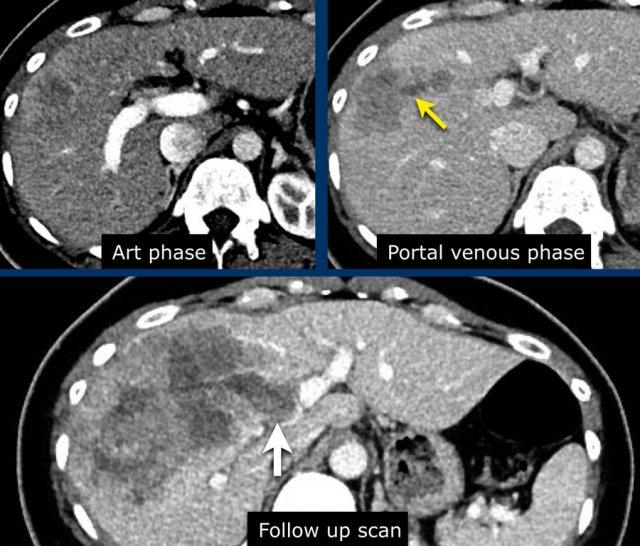

Đây là hình ảnh thì động mạch muộn của một bệnh nhân xơ gan.

Ghi nhận một tổn thương có tăng ngấm thuốc không dạng viền (mũi tên vàng).

Ở thì muộn, tổn thương có hiện tượng washout.

Đây là những đặc điểm điển hình của HCC.

Tổn thương còn lại (mũi tên xanh lá) là tổn thương đã được điều trị, sẽ được thảo luận ở phần sau.

Hình ảnh thì động mạch, thì tĩnh mạch cửa và thì muộn của một tổn thương LIRADS 3.

Tại phân thùy 5 có một tổn thương dưới bao gan với ngấm thuốc động mạch mạnh mà không có thải thuốc ở thì tĩnh mạch cửa hoặc thì muộn.

Các hình ảnh cho thấy một tổn thương ngấm thuốc động mạch có thải thuốc ở phân thùy VI, nghi ngờ HCC: LR-5.

Lưu ý rằng sự ngấm thuốc động mạch mờ nhạt do bệnh nhân được chụp ở thì động mạch sớm thay vì thì động mạch muộn – thì mà HCC đạt đỉnh ngấm thuốc.

Do đó, các tổn thương nhỏ bổ sung có thể dễ dàng bị bỏ sót.

Một CT theo dõi được thực hiện, cho thấy tiến triển nặng của khối u cũng như xâm lấn mạch máu vào nhánh tĩnh mạch cửa phải trước (mũi tên trắng).

Lúc này chúng ta có thể xác định chắc chắn sự xâm lấn khối u vào tĩnh mạch cửa.